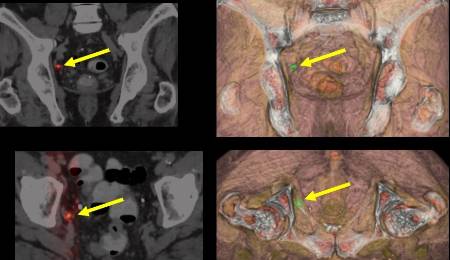

- Exploración PET-TAC: esta prueba, que es uno de los mayores avances en medicina nuclear, permite detectar tumores precozmente y con mayor fiabilidad, así como conocer su extensión. Combina la tecnología del TAC con la utilizada en el PET para ofrecer imágenes tridimensionales de los órganos. Utiliza compuestos inocuos, como por ejemplo la glucosa, que se depositan más en tejidos metabólicamente ineficientes como muchos tumores, entre otros.

- Exploración PET-RM: unifica en un solo proceso la información de los procesos moleculares que ofrece el PET y la morfofuncional de los tejidos que aporta la resonancia magnética (RM).